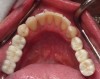

Figure 2 If the Schick CDR sensor is compared to the most recent Schick 33 sensor, dramatic differences can be seen in resolution and image file size. Both images were taken at the default settings and were not manipulated. The actual size of the images was taken from the image descriptions in the software; the Schick CDR sensor image is under 400 kilobytes, whereas the newer Schick 33 sensor image is over 4 megabytes, which is more than 10 times larger.

Figure 3. If the Schick CDR sensor is compared to the most recent Schick 33 sensor, dramatic differences can be seen in resolution and image file size. Both images were taken at the default settings and were not manipulated. The actual size of the images was taken from the image descriptions in the software; the Schick CDR sensor image is under 400 kilobytes, whereas the newer Schick 33 sensor image is over 4 megabytes, which is more than 10 times larger.

Are There Differences with Intraoral Digital Sensors?

Mouyen et al12 introduced the first digital sensor in 1989 with a direct image produced on thermal paper that was revolutionary but barely diagnostic. Image quality has improved significantly with direct digital sensors and photostimulable plates each providing diagnostic quality images, but some studies still conclude that digital radiology is slightly inferior to conventional dental x-ray film.13 These comparisons are always difficult because dental film is static and digital images are dynamic when manipulated with the imaging software, actually making digital images more diagnostic because clinicians have the ability to extrapolate more information from the image with software tools. If the Schick CDR sensor is compared to the most recent Schick 33 sensor, dramatic differences can be seen in resolution and image file size (Figure 2 and Figure 3). Both images were taken at the default settings and were not manipulated. The actual size of the images was taken from the image descriptions in the software; the Schick CDR sensor image is under 400 kilobytes, whereas the newer Schick 33 sensor image is over 4 megabytes, which is more than 10 times larger. Compare this with a digital camera photograph of 4 megabytes to one that is 4 kilobytes; the smaller image shows a lot of pixilation when you zoom in. A 10 times increase in image size shows the inherent improvement in the technology. The software features provide significant diagnostic enhancement for the need to differentiate between the tissue types, ie, bone, dentin, enamel, cementum, etc.